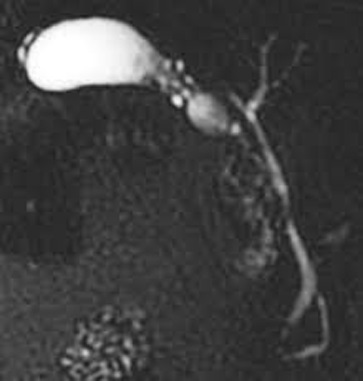

Image IRM et cholagio-IRM

: Technique interessente pour distingue une

adenomyomateuse et d'une neoplasie de la vesicule biliaire .

Les sinus de Rokitansky -Aschoft sont hypointense sur T1 et

hyperintense sur T2 . La cholangio -IRM se

donne de image de la vesicuule biliaire a paroi epais

diffusee ou localisee et image de " collier de perles

"

Image de " collier de perles

d'une adenomyomatose vesiculaire forme diffuse :

Image IRM ponderee surT2 en coupe coronal |

Image cholangio- IRM d'une

adenomyomatose vesiculaire : Les sinus de

Rokitansky-Aschoff sont hyperintense en forme de "

collier de perles" a infundibulum vesiculaire . |